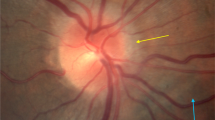

This increased ICP may explain the pathologic changes observed in SANS such as optic nerve sheath expansion, axoplasmic flow stasis, and globe flattening6. However, flight crew do not present with other typical signs of elevated ICP such as bilateral papilledema and headaches which has prompted further investigation of the potential role of ICP in pathogenesis of SANS6. Further, all astronauts experience the headward fluid shift associated with chronic weightlessness but only approximately 15% of astronauts develop Frisèn grade optic disc edema based on fundoscopic imaging16.

Although evidence exists for increased ICP post spaceflight6, the mechanisms of damage remain ambiguous. Recent studies have shown that the relationship between ICP and intraocular pressure (IOP) is critical in the pathogenesis of optic nerve diseases17,18. Previously, a canine model demonstrated that by controlling IOP and CSF pressure changes, there can be large displacements of the optic disc19. Elevating CSF pressure in porcine eyes has also shown increased principal strain within the lamina cribrosa region and retrolaminar neural tissue20. This increased strain on the retinal ganglion cells (RGCs) within the lamina cribosa region can contribute to axonal transport blockage and loss of RGCs20. A recent study on astronauts also suggested an anterior shift due to a pressure differential between ICP and IOP may contribute to SANS as indicated by optic nerve lengthening and anterior movement of the optic nerve head (ONH)21.

Additionally, ICP typically follows a diurnal pattern on Earth as it fluctuates with positional changes22. Thus, it has been suggested that the absence of diurnal variations under conditions of microgravity causes the ICP to be mildly elevated at pressures between upright and supine pressures on Earth17. Under conditions of microgravity, the mild increase in ICP due to lack of diurnal variations could lead to lower translaminar pressure gradients at the posterior end of the eye. The long-term lower gradient exposure would subsequently lead to optic nerve head (ONH) remodeling and result in the subsequent pathologic changes observed in SANS.

The various pressure conditions were determined from previously published data5,7,8,9,10. On Earth, ICP is lower when seated in the 90° upright posture compared to supine (seated, 4 ± 1 vs. supine, 15 ± 2 mmHg). On the contrary, under conditions of acute zero gravity, ICP is reduced but not to the levels of an upright position on Earth (supine, 17 ± 2 vs. microgravity, 13 ± 2 mmHg). The prolonged exposure to microgravity does not cause a pathogenic elevation in ICP (supine, 15 ± 2 vs. 24 h head‐down tilt, 15 ± 4 mmHg) but instead it prevents the normal lowering of ICP when upright17. This chronic, mild elevation in ICP, does not subside under microgravity conditions and can adversely affect eye structure and function during prolonged space flight22. In addition to ICP, the IOP is also seen as instantaneously elevated during parabolic flights under acute microgravity exposure. A 5 mmHg increase in IOP is observed through the free-fall phase of parabolic flight from a mean baseline value of 12 mmHg to 19 mmHg within 20 s of exposure to microgravity25. It has been shown that during short-duration flights, the IOP initially elevates during the first few days and then drops below preflight levels on return to Earth26. Under stimulation studies, IOP during a 6° HDT bed rest study for 7 days has shown an initial immediate rise in IOP after which there has been a slight and progressive decrease by 1.3 mmHg27. Variable reports on IOP changes during 6° and 10° HDT in humans have shown variable responses with increase in IOP and ICP through short-term studies27,28. Although long-term monitoring of HDT has not been performed in humans.